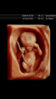

Wow!! Åssen bilder er det her? Helt utrolig flotte! :O ❤❤Vis vedlegget 139616Vis vedlegget 1396172 av de fantastiske bildene vi fikk idag. 13+4 i følge menstermin.

Ny teknologi! Jeg har altså så mange kule, flotte og fantastiske bilder!!!Wow!! Åssen bilder er det her? Helt utrolig flotte! :O ❤❤

Jeg var hos Martin Lundring på spesialistsenteret for kvinner på Jessheim. Det kosta, men fikk jo sykt mange bilder og en flott time med full gjennomgang av alt.Steike, helt fantastisk! Hvem driver med denna teknologien da?!!![]()

Er det dette som er 3d UL?Jeg var hos Martin Lundring på spesialistsenteret for kvinner på Jessheim. Det kosta, men fikk jo sykt mange bilder og en flott time med full gjennomgang av alt.

Ja, men en utbedret form med en ny teknologi.Er det dette som er 3d UL?

Oppdaget akkurat at det er 4D.Ja, men en utbedret form med en ny teknologi.